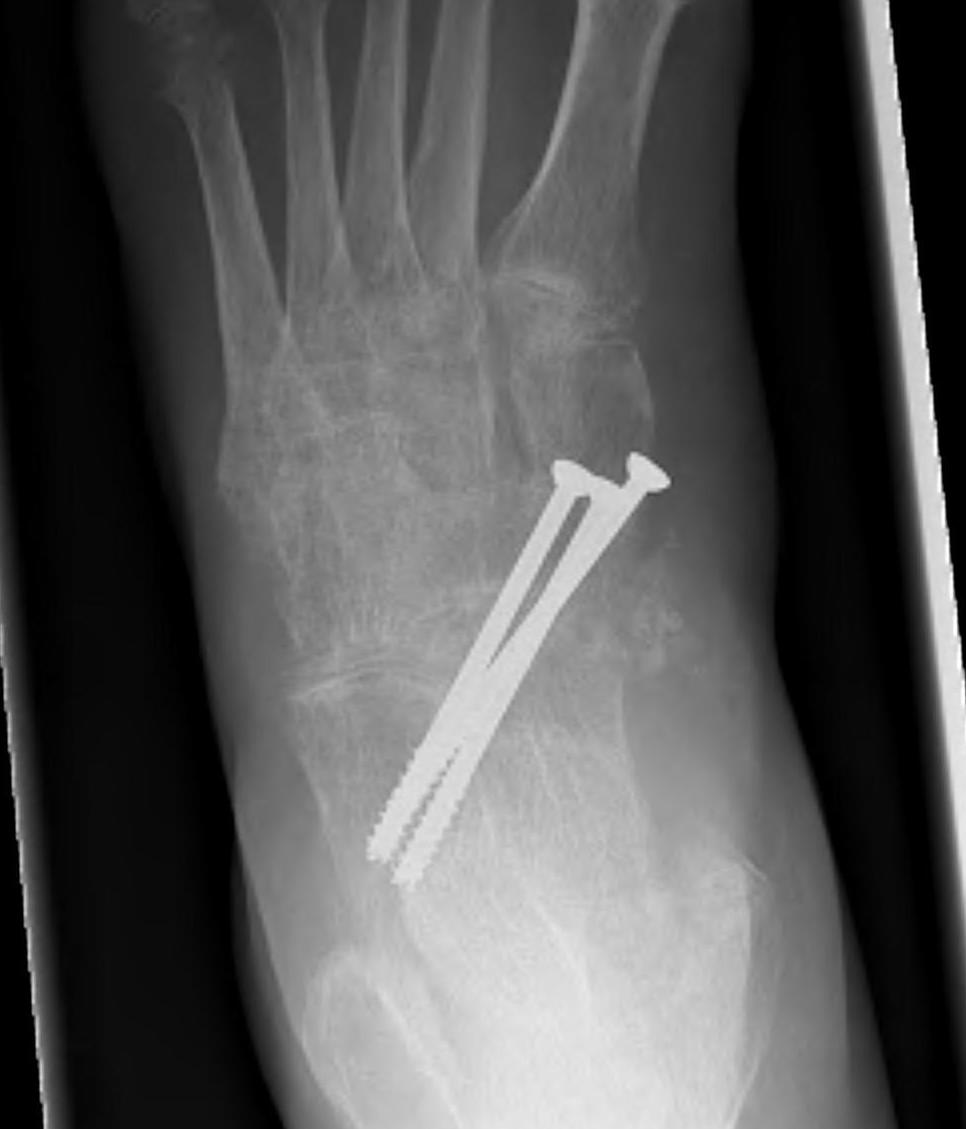

Talonavicular arthrodesis

Arthroscopic technique isolated TN arthrodesis

Goh et al Foot Ankle Surg 2022

- 40 cases of isolated TN arthrodesis

- higher fusion rates with plate + screws versus screws alone